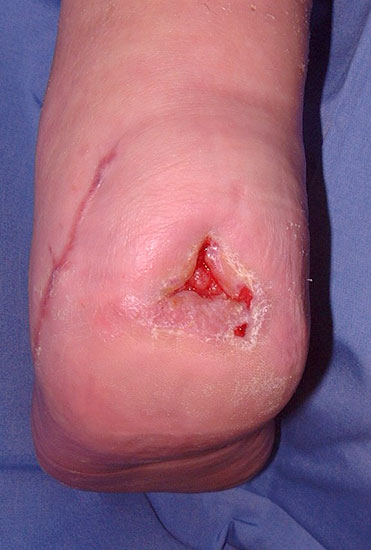

Wundverschluss

Der Wundverschluss erfolgt nach Einlegen eine Drainage durch lockere Subkutan- und Hautnähte. Bei schweren Infektionen bleibt die Wunde offen. Es empfiehlt sich ein Verband mit mäßiger Kompression, um Sickerblutungen zu stillen. Sobald eine infektfreie Granulation des Wundgrundes eingetreten ist, erfolgt der finale Wundverschluss. Dabei ist darauf zu achten, keine Hohlräume in der Tiefe zu belassen. Geringe Wunddehiszenzen verschließen sich spontan (Abb. 36, 37).